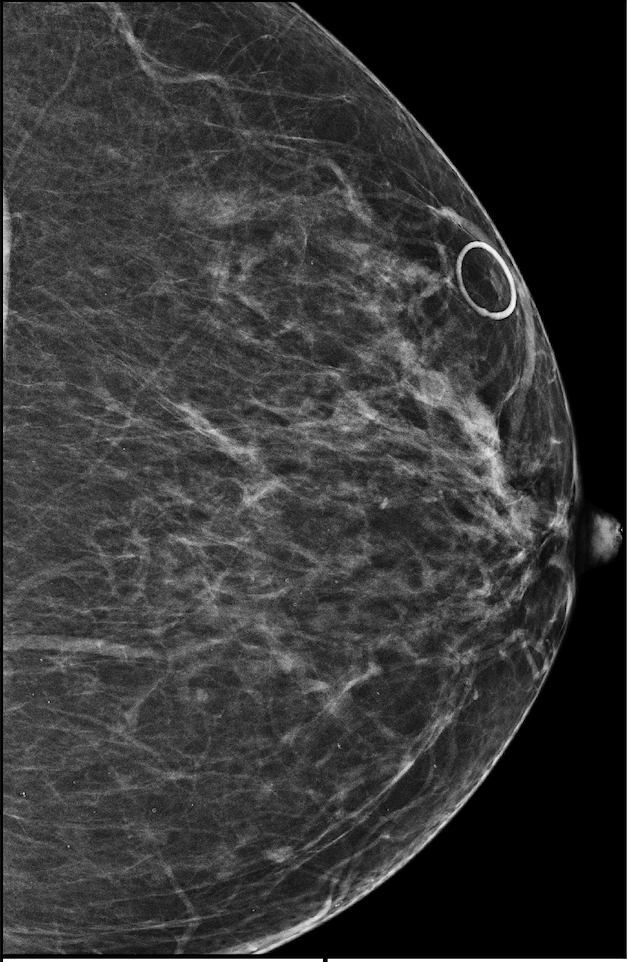

To better understand our model’s behavior, we visualize SMs of three samples selected from the test set in Figure 4. In the first two examples, the SMs are highly activated on the true lesions, suggesting that our model is able to detect suspicious lesions without pixel-level supervision. Moreover, the attention is highly concentrated on ROI patches that overlap with the annotated lesions. In the third example, the malignant SM only highlights parts of a large malignant lesion. This behavior is related to the design of : a fixed pooling threshold cannot be optimal for all sizes of ROI. Furthermore, this observation also illustrates that while human experts are asked to annotate the entire lesion, CNNs tend to emphasize only the most informative part.